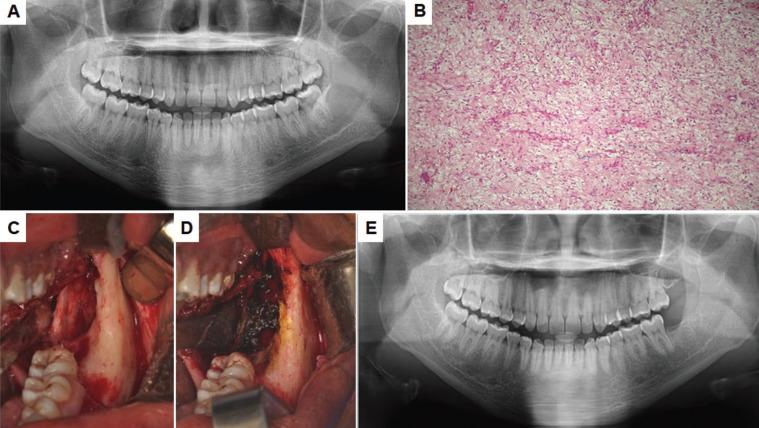

There was a mild preference for the male with a mean age of 22.8 years. Seventy-seven percent of the lesions occurred in the posterior region of the mandible, presenting a multilocular radiolucent aspect (54%) with one presenting symptomatology. Conservative treatment was performed in all patients initially and recurrence was observed in two cases.

Odontogenic myxoma has a well-defined clinical profile and the choice of treatment should consider aspects such as patient's age, lesion size, and location. Myxoma, odontogenic tumors, diagnosis, treatment.

男性略占优势,平均年龄22.8岁。77%的病变发生在下颌骨后部,呈现多房性透射影(54%),1例有症状表现。所有患者最初均接受保守治疗,2例出现复发。

牙源性黏液瘤具有明确的临床特征,治疗选择应考虑患者年龄、病变大小和位置等因素。黏液瘤、牙源性肿瘤、诊断、治疗。